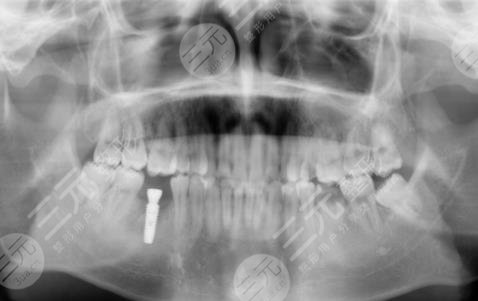

三、镇江口腔医院种植牙经历分享

因为我真的十分喜欢吃糖,也就是很喜欢甜食,几乎每天都有很多的糖摄入,有的时候连吃米饭我想要吃甜的,这就导致了我的年纪轻轻牙齿就蛀了,因为糖吃多了,刚开始的时候还只是进行补牙,但是随着时间越来越久,我的牙齿的孔洞越来越大,然后没有办法就是拔掉了,我想着一直去补也不是问题,就跟父母商量之后,来到了镇江口腔医院进行种植牙。

医生看了我的牙齿情况之后,为我判断了几颗比较需要进行种植牙的地方进行了拔除。大概在拔完牙,一星期后我进行了种植牙,刚种上的时候还是觉得挺不舒服的,但是随着时间的推移,我逐渐适应了自己的种植牙,并且种植的牙齿比之前更加洁白,它不单单解决了我的口腔问题,还让我整个人的气质都上升了不少呢。